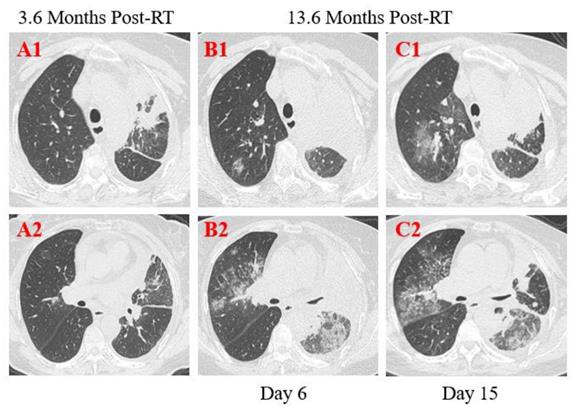

Figure 2

Transverse thin-section serial CT scans from a 53-year-old male with suspected COVID-19 pneumonia. Serial CT scans showed pericardial effusion, multiple enlarged lymph nodes in the mediastinum, scattered, multiple, similar round thin wall/no wall transparent areas (A2, B2, C3), smooth or nodular interlobular septal thickening (A1, B1), and multiple nodules in the dorsal segment of the lower lobe of both lungs with spotted calcifications and adjacent pleural thickening (A2, A3). Chest CT images performed at the 10th day after symptom onset showed patchy areas of consolidation co-existed with ground-glass opacities (A3), or linear scarring with discrete consolidation (A2), air bronchograms (A1), and irregular intralobular or interlobular septal thickening (A1-3, A3). Follow-up CT at the 13rd day demonstrated partial improvement (B1) but primarily increment in the extent and density (B2, B3), continued segmental consolidations and atelectasis in the lower lobe of both lungs (B3).

Patient 1: A 53-year-old male was diagnosed with middle and lower esophageal squamous cell carcinoma with multiple bone metastases staged with T4aN2M1 and began to receive palliative concurrent chemoradiotherapy on September 29, 2016, and admitted to the hospital on January 28, 2020. He had sputum production and cough of more than ten days duration, and a little bit hemoptysis of two days duration. He also felt fatigued, chest distress, vomiting after eating, but no fever. He was neither from the infected area nor contacted with infected peoples. The physical examination revealed coarse breath sounds during auscultation, and laboratory studies showed normal leukocyte, but lymphopenia and serious thrombocytopenia. Also, markly elevated concentrations of D-dimer, Procalcitonin (PCT), C-reactive protein (CRP), and N-terminal-pro hormone brain-type natriuretic peptide (NT-BNP) were observed at admission. Results of serial CT scans showed pericardial effusion, multiple enlarged lymph nodes in the mediastinum, scattered, multiple, similar round thin wall/no wall transparent areas (Figure 2. A2, B2, C3), smooth or nodular interlobular septal thickening (Figure 2. A1, B1), and multiple nodules in the dorsal segment of the lower lobe of both lungs with spotted calcifications and adjacent pleural thickening (Figure 2. A2, A3). Above lung lesions were approximately the same as before. Moreover, compared with the previous CT scan 12.6 months before, chest CT images performed at the 10th day after symptom onset showed the obviously progressive lung lesions including patchy areas of consolidation co-existed with ground-glass opacities (Figure 2. A3), or linear scarring with discrete consolidation (Figure 2. A2), air bronchograms (Figure 2. A1), and irregular intralobular or interlobular septal thickening (Figure 2. A1-3) in the lower lobes of both lungs adjacent to the mediastinum conforming completely to the irradiated area. It was suggested the possibility of RILI, interstitial pneumonia or viral pneumonia. After 3 days of anti-infective therapy with tazocin, moxifloxacin, and arbidol, combined with aggressive supportive care, follow-up CT demonstrated partial improvement (Figure 2. B1) but primarily increment in the extent and density of lung lesions (Figure 2. B2, B3), and continued segmental consolidations and atelectasis were observed in the lower lobe of both lungs (Figure 2. B3). Repeated three times of swab nucleic acid tests for the COVID-19 were negative, and he ultimately was excluded. Afterward, the patient was transferred to the Department of Oncology to continue treatment to reduce the burden of the frontier department.